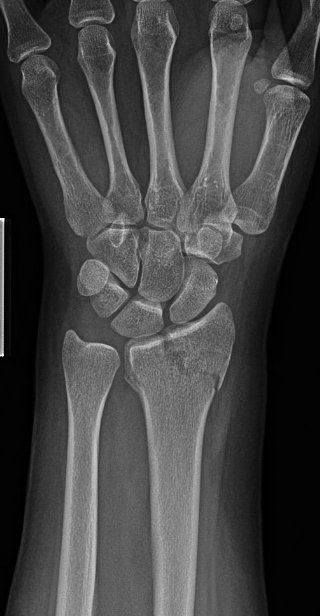

Scope assisted reduction of the articular surface was pretty cool, but radiographs honestly showed the same story

Ordinarily, I’d change that long/distal screw out, but since I was scoping the joint and didn’t see penetration, I felt ok leaving it

Debrided and pinned the SL